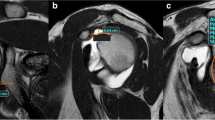

The measurement of the critical shoulder angle (CSA) was adapted to MRI as previously described by Spiegl et al. [20]. As the most lateral point of the acromion is usually located posteriorly to the glenoid the most lateral extent of the acromion in a coronal plane is marked with the cursor (see Fig. 2). After scrolling back to a plane that shows the glenoid and more central parts of the acromion, the critical shoulder angle was measured [20].

Measurement of the critical shoulder angle. T1-weighted images in a coronal plane a, b. Transversal proton-density weighted fat saturated images c. The most lateral extent of the acromion is marked in a coronal plane (arrow in a). After scrolling to a coronal plane, representing the middle of the glenoid b, the critical shoulder angle was measured. The white line in c represents the imaging plane of b

Although involving scrolling through different imaging planes (see Fig. 2), adaption of the critical shoulder angle from conventional radiographs to MRI is a reliable measurement with almost perfect interrater variability (κ = 0.829; p < 0.001). This is remarkable since other authors only reported an inter-observer agreement of 0.62 for their method of measuring the critical shoulder angle [20]. One reason for this might be that other study populations consisted to one third of patients with osteoarthritis of the glenohumeral joint making it hard to identify the cranial and caudal border of the glenoid, which is needed for measuring the critical shoulder angle [20]. So the accuracy of measuring CSA in Impingement/rotator cuff populations seems to be more valid than in case of other pathologies.